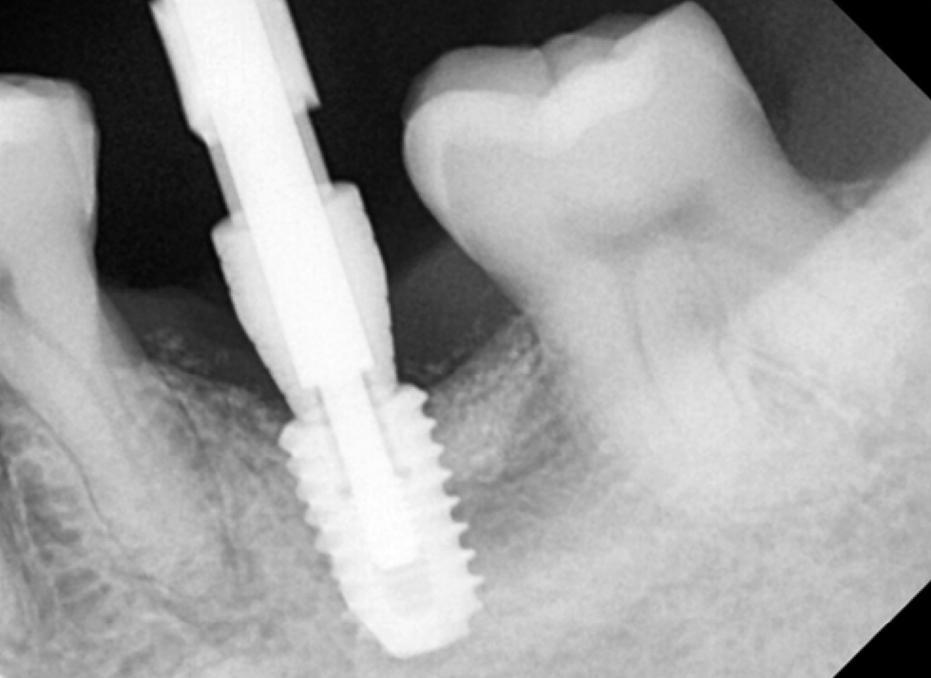

기다리는 동안 오른쪽 아래 어금니를 진행합니다.

오른쪽 아래는 발치한 지 오래되었고,

염증은 없는 상태라 뼈이식 없이 임플란트 식립을 진행하였습니다.

2개월 후 보철을 올릴 수 있을 것으로 판단하였습니다.